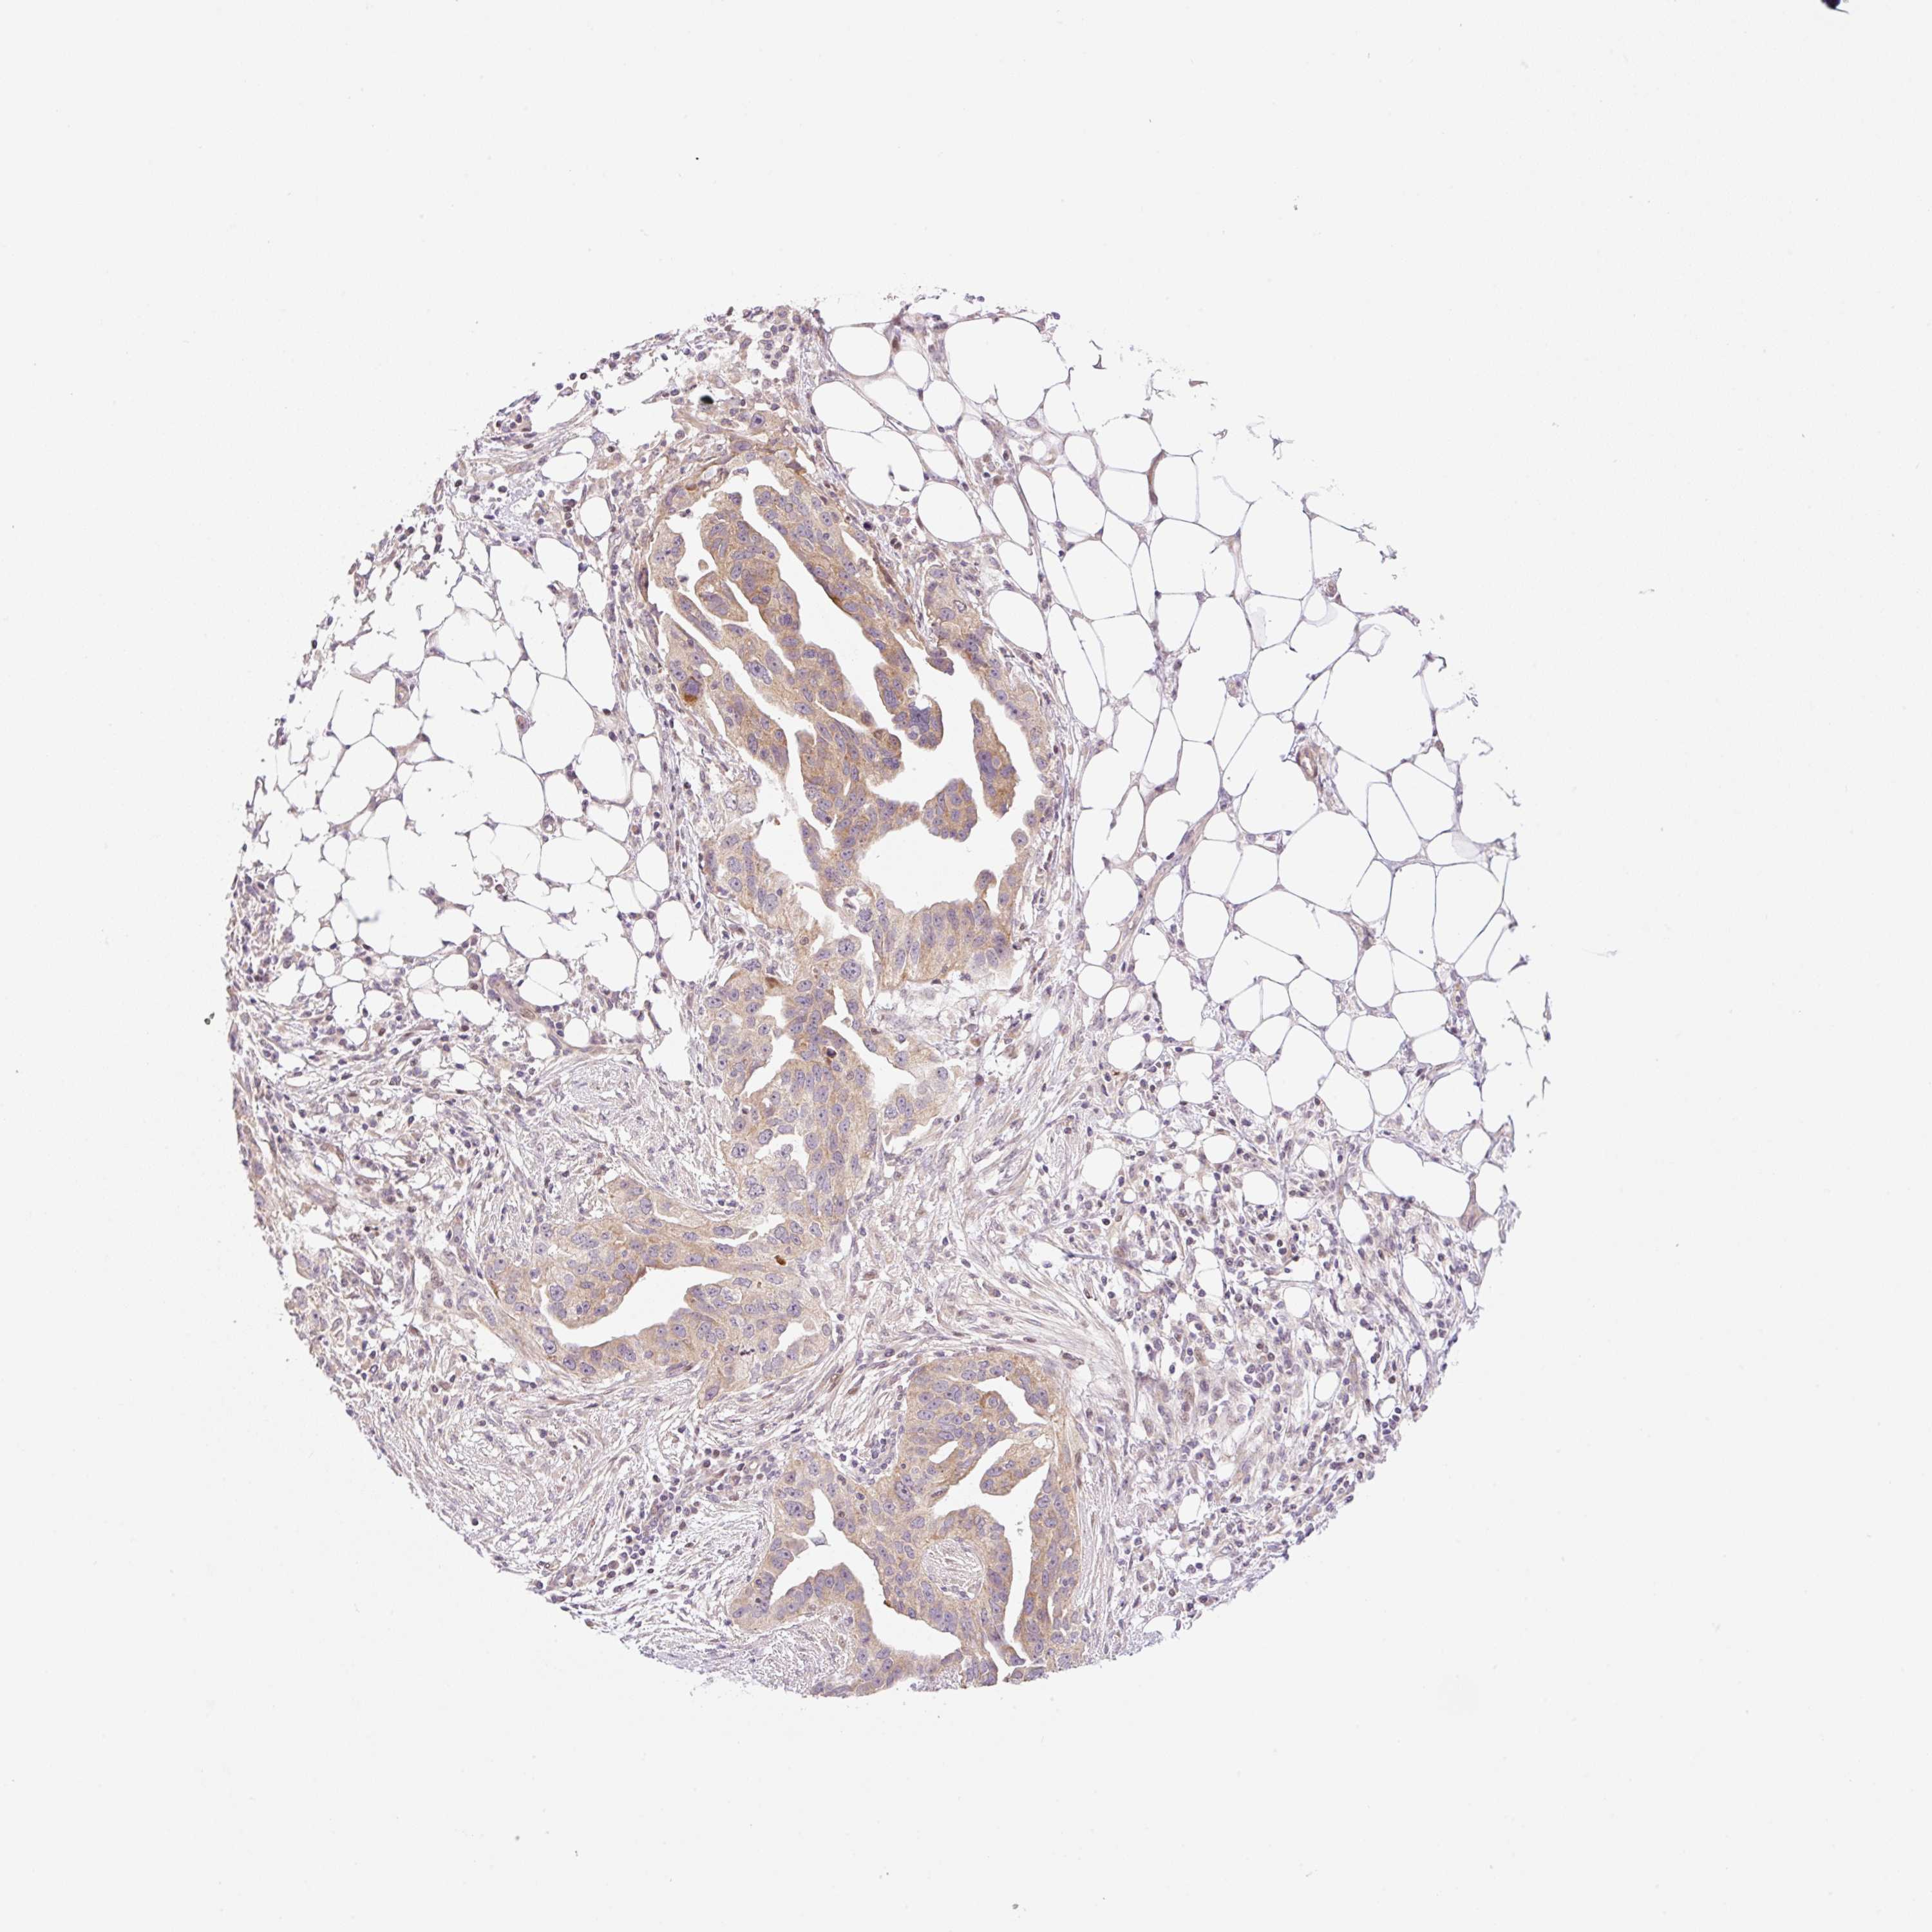

OVARIAN CANCER - Protein expressioni

A mouse-over function shows sample information and annotation data. Click on an image to view it in a full screen mode. Samples can be filtered based on level of antibody staining by selecting one or several of the following categories: high, medium, low and not detected. The assay and annotation is described here.

Note that samples used for immunohistochemistry by the Human Protein Atlas do not correspond to samples in the TCGA dataset.

Antibody stainingi

Antibody staining in the annotated cell types in the current human tissue is reported as not detected, low, medium, or high, based on conventional immunohistochemistry profiling in selected tissues. This score is based on the combination of the staining intensity and fraction of stained cells.

Each image is clickable and will lead to virtual microscopy that enables deeper exploration of all samples and also displays staining intensity scores, fraction scores and subcellular localization as well as patient and tissue information for each sample.

Antibody HPA051421

Antibody HPA054639

Cystadenocarcinoma, serous, NOS